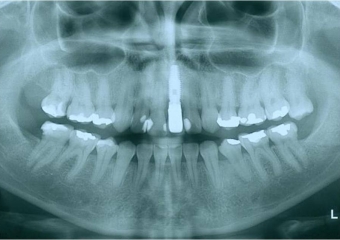

Raio X inicial do dente 21 fraturado